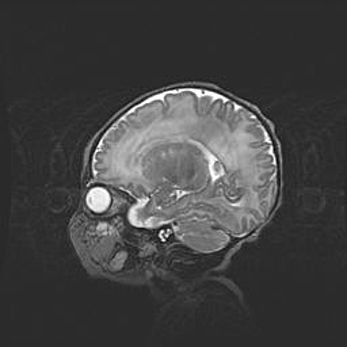

Подострая гематома правой гемисферы мозжечка.

Наружная гидроцефалия.

Возраст: 15 дней

Вес: 3100 г

Пол: женский

Окружность головы: 37 см

Срок гестации: 35-36 недель

При открытой наружной форме гидроцефалии у новорожденных расширяются и переполняются субарахноидные пространства.

Кровоизлияния в мозжечок имеют две клинико-анатомические формы: полушарные гематомы и кровоизлияния в червь.

К появлению этой патологии может привести: повреждения головного мозга, возникающие в результате асфиксии и гипоксии плода при беременности, или травмы во время родов. Редко гематома мозжечка может быть результатом первичной коагулопатии и сосудистой мальформации, диссеминированном внутрисосудистом свертывании, изоиммунной тромбоцитопении.